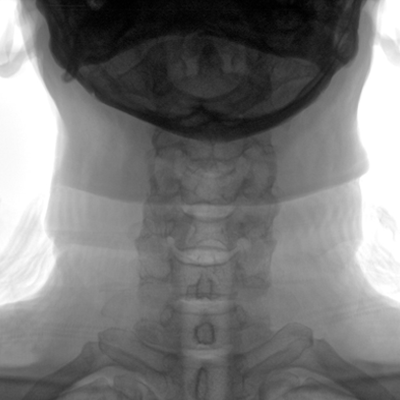

臨床適用科室:骨科、普通外科、矯形外科、創傷外科、泌尿外科、脊柱外科、疼痛外科、消化科、婦科等科室。

大尺寸動態平板探測器,高DQE、低噪聲、圖像清晰。采用多分辨率圖像增強處理技術,不同部位不同圖像處理算法,滿足客戶多樣化的需求。

采用智能變頻脈沖透視技術,優化圖像質量的同時降低輻射劑量,呵護醫患健康